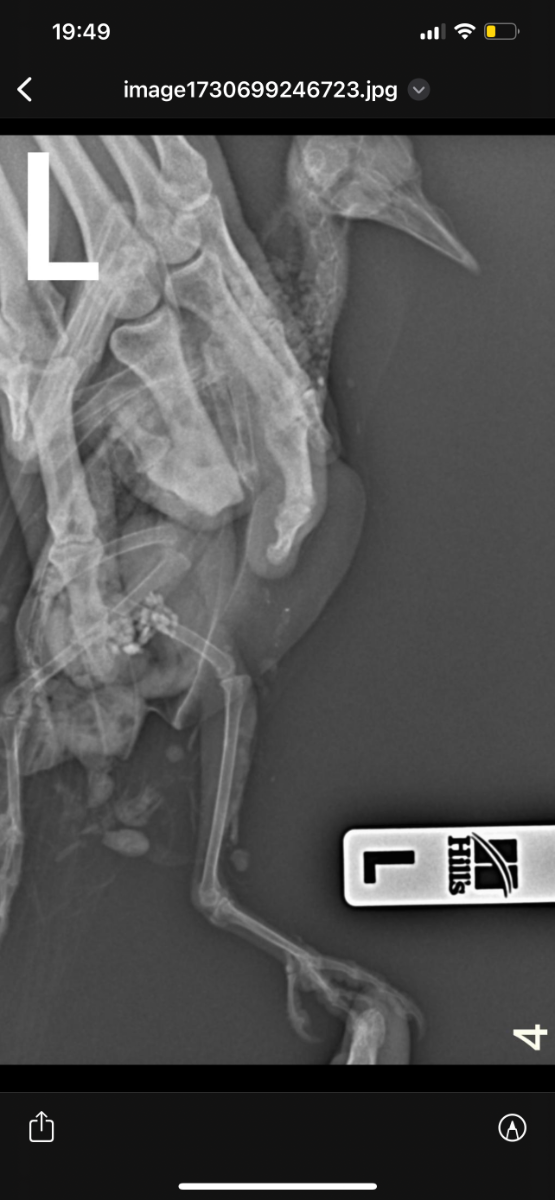

Здравствуйте, неделю назад возле автомобиля обнаружила голубя , лежал на левом боку и не мог встать. Я подумала что сбила машина, взяла его к себе. Съездили к орнитологу , он пощупал лапки , сказал возможно это связано с нервной системой , либо повреждена левая лапа. Голубь, взлетает без проблем. Но не упирается на лапы , теряет координацию и падает + постоянно вся попа в 💩. Кушает хорошо и пьет водичку самостоятельно. Сегодня смотрю , упирается на правую лапу , а левую вытягивает прямо назад.

На всякий случай купила витамины, добавляю по капельки в водичку. Голову не запрокидывает.  Фото рентгена прилагаю. Кто сталкивался с подобным ? Что может быть ?

Возможно есть повреждение бедренной кости- выбита или перелом головки.